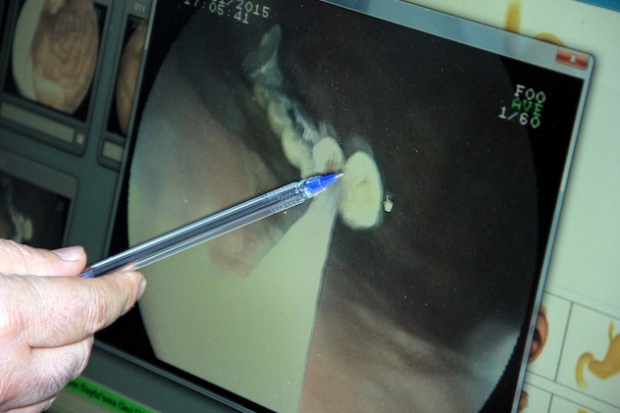

Gaziantep’te nohut dürümü yediği sırada 5 dişinin eksildiğini fark eden kişinin 5 dişi bağırsaklarında bulundu.

Gaziantep’te nohut dürümü yediği sırada 5 dişinin olmadığını fark eden 54 yaşındaki A.B., Dr. Ersin Aslan Devlet Hastanesinde muayene olduktan sonra kaybolan 5 dişi midesinden çıktı. Ameliyatı gerçekleştiren Gastroenteroloji Uzmanı Dr. Ahmet Yağbasan, “Cumartesi günüydü, bir tane diş yutma vakası olduğu söylendi. Öncellikle biz onu tam protez zannettik. Tam protez olsaydı. Biz onu çıkaramayabiliriz dedik. Daha sonra telefondan resmini gönderiler. Midede beş dişlik bir protez olduğunu gördük. Onu çıkarabiliriz diye düşündük. Normal filmde midede olduğu görünüyordu. Ama mideye baktığımızda dişleri göremedik. Dolayısıyla ilerlemiş olabileceğinin düşündük. Hastayla konuştuk nasıl olmuş diye, Antep nohut dürümü yerken dişinin eksik olduğunu hissetmiş. Bağırsak tıkanıklığına neden olabilecek bir protezdi. Yaklaşık 3 saat ameliyat sonrası dişleri çıkardık” şeklinde konuştu.